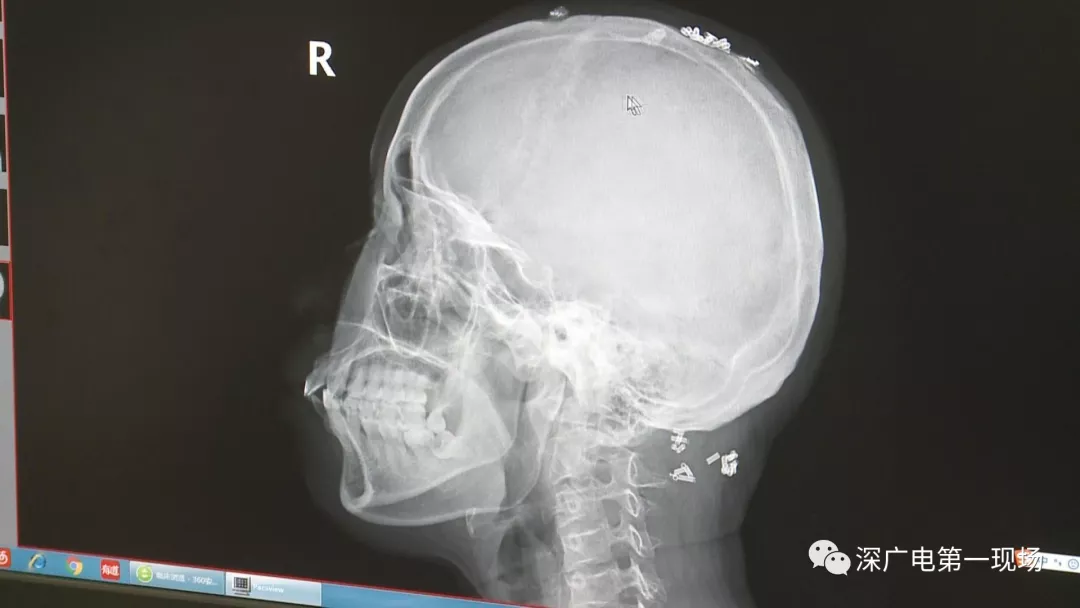

彈簧圈已“寄生”三年

部分形成包塊難以取出

據了解,這位患者周身的彈簧圈已經固定了三年多,因為患者感覺治療效果不好,就來深圳求醫(yī)。